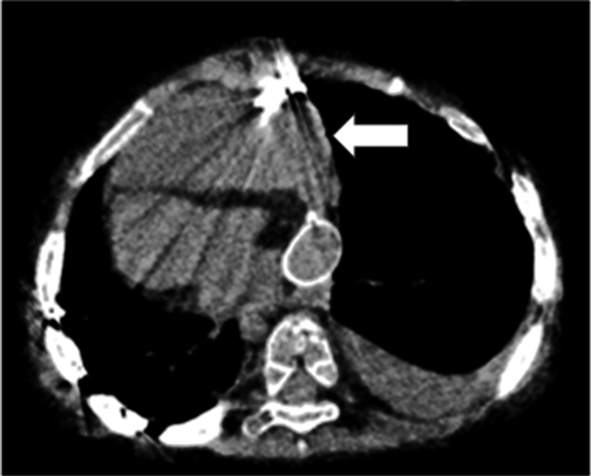

Pediatric Cardiology and Cardiac Surgery 37(4): 320-328 (2021)

Fig. 8 Image of computed tomography on postoperative day 9

The hemorrhage (arrow) emerged and compressed the heart.

術後8日目から発熱と洞性頻脈が出現した.心エコー検査では収縮良好で心嚢液はなく,血液検査でAPTTは45.9 secと延長はなかった.炎症反応上昇を認め術後感染を疑い抗菌薬を開始した.術後9日目も頻脈が持続し,心エコー検査の再検で心臓前面の液体貯留を認めた.CTにて心臓前面に血腫が存在し心タンポナーデと診断した(Fig. 8).血液検査でAPTT 135.0 secと著明に延長していた(Fig. 9).